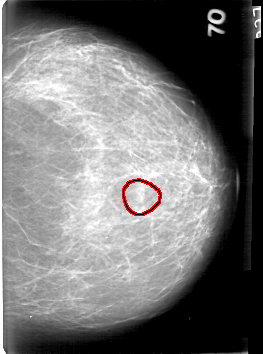

D_4086_1.LEFT_MLO

LEFT_MLO LINES 5296 PIXELS_PER_LINE 4051 BITS_PER_PIXEL 12 RESOLUTION 43.5 OVERLAY

FILE: D_4086_1.LEFT_MLO.OVERLAY

TOTAL_ABNORMALITIES 1

ABNORMALITY 1

LESION_TYPE MASS SHAPE OVAL MARGINS OBSCURED

ASSESSMENT 0

SUBTLETY 4

PATHOLOGY BENIGN

TOTAL_OUTLINES 1

BOUNDARY